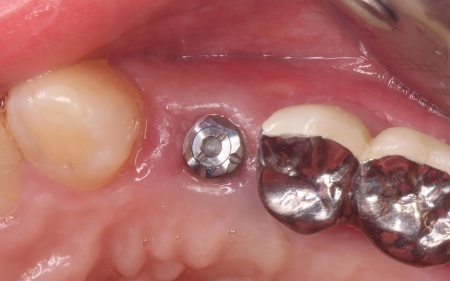

治療中